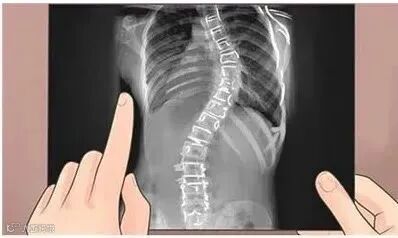

——“脊柱侧弯20度。”

正常人的脊柱从后面看应该是一条直线,并且躯干两侧对称。如果脊柱偏移躯干中线,X光片上的弯曲角度(Cobb角)大于10°时,就称之为脊柱侧凸,俗称脊柱侧弯。